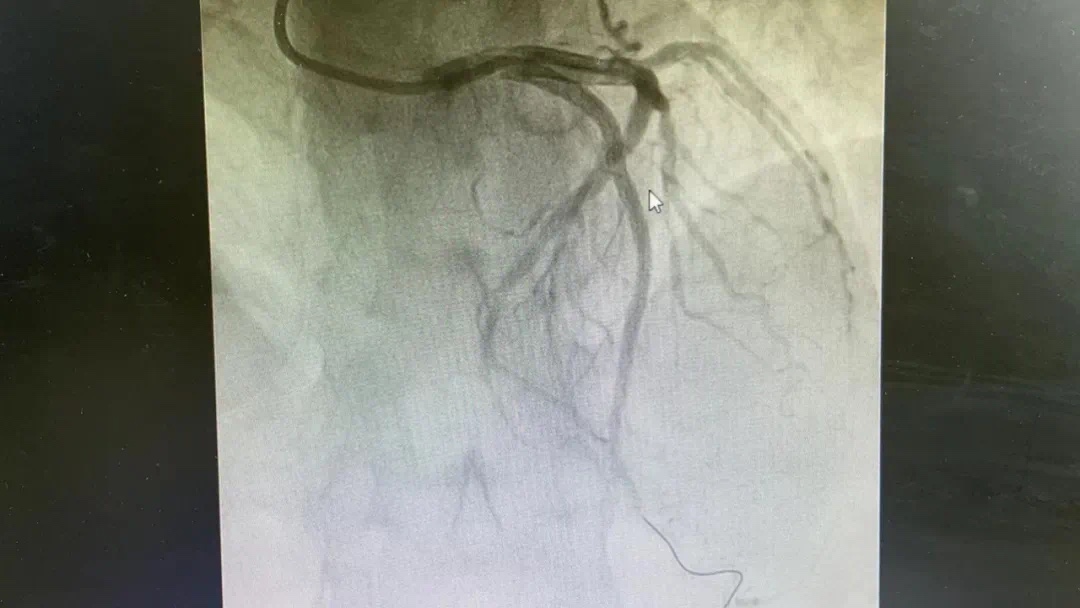

术前、术后图片如下

副主任何涛、医师熊俊锋、护士张梅梅顾不上休息,立刻投入到第三次抢救中。胸痛中心团队心内科与急诊科无缝衔接,23点26分在导管室开通堵塞血管,又成功救治一名急性心肌梗死患者。患者张某送至导管室施行急诊冠脉介入治疗,经过快速的术前准备,以mini Crush术式于回旋支远段植入波科冠脉支架一枚,再于钝缘支中段至回旋支中段植入Firebird2冠脉支架一枚。患者症状大幅缓解。零点42分手术结束,复查患者血压、心率正常后将患者送回病房。